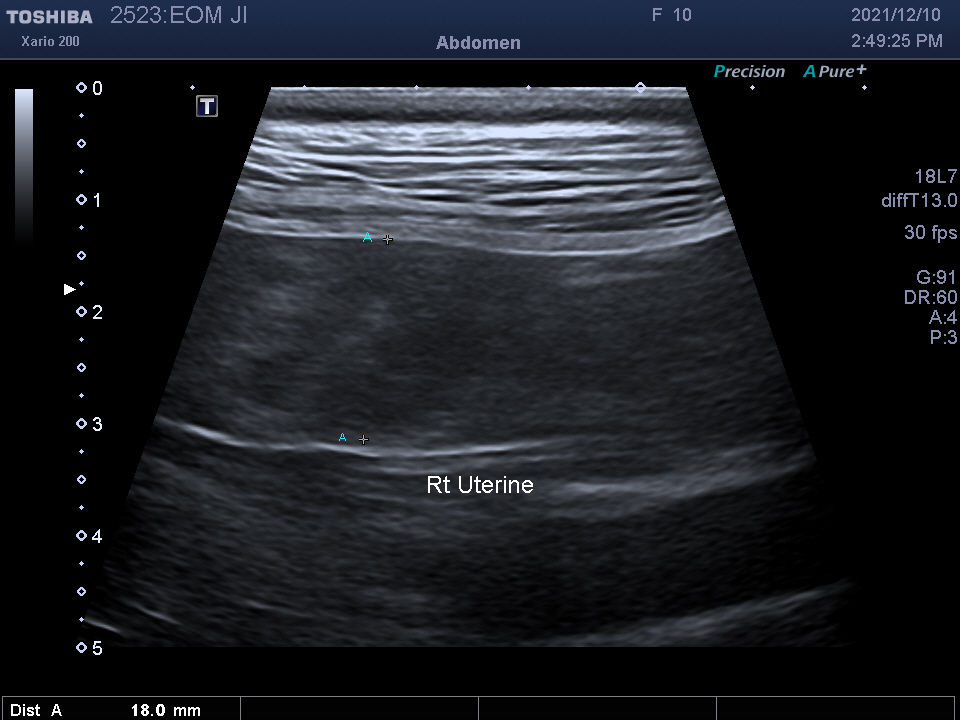

복강 내 장기를 자세히 알 수 있는

복부 초음파 검사를 진행하였습니다.

검사 결과를 종합하여 자궁 축농증이라는 진단을 받았습니다.